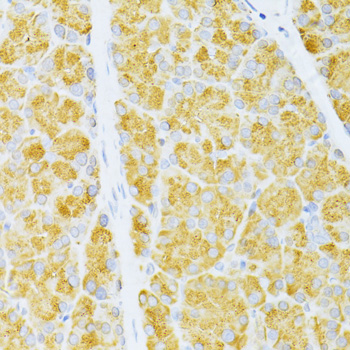

Immunohistochemistry of paraffin-embedded rat pancreas using FLT3 at dilution of 1:100 (40x lens).

Immunohistochemistry of paraffin-embedded human liver cancer using FLT3 at dilution of 1:100 (40x lens).